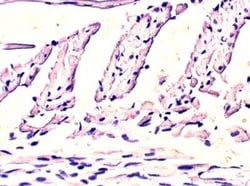

EHD4 Polyclonal antibody specifically detects EHD4 in Human, Mouse, Rat samples. It is validated for Western Blot, ELISA, Immunohistochemistry, Immunoprecipitation, Immunohistochemistry (Paraffin)Specifications

| Western Blot 1:500, ELISA 1:10000, Immunohistochemistry 1:100, Immunoprecipitation 1:200, Immunohistochemistry-Paraffin 1:100 | |

| Western Blot, ELISA, Immunohistochemistry, Immunoprecipitation, Immunohistochemistry (Paraffin) | |